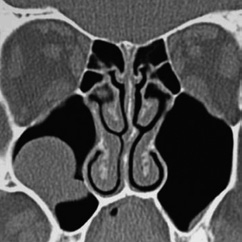

Anatomie und Funktion der NNH Die Nasennebenhöhlen (NNH) sind mit Schleimhaut ausgekleidete knöcherne Hohlräume, die über enge Spalten und Öffnungen mit der Nasenhaupthöhle in Verbindung stehen. Über diese Spalträume besteht eine permanente Ventilation und eine dauerhafte Sekretdrainage. Die Durchgängigkeit dieser Belüftungs- und Drainagewege ist maßgeblich für eine normale Funktionsweise der Nasennebenhöhlen verantwortlich, die somit die Klimafunktion der Nase mit Anfeuchtung und Erwärmung der Atemluft unterstützt. Daneben wird den NNH auch ein Beitrag zur Verminderung des Gewichts des Gesichtsschädels, als Pufferzone zum Schutz des Hirns bei Kopftraumen sowie ein Effekt für die Sprachresonanz und als Pufferzone zum Schutz des Hirns bei Kopftraumen zugeschrieben [1].

Obwohl aus pathophysiologischer Sicht das Siebbein und der mittlere Nasengang die wichtigsten anatomischen Strukturen bei der Genese entzündlicher Nasen- und NNH-Erkrankungen sind, manifestieren sich die Krankheitssymptome häufig spürbar im Bereich der Kieferhöhle und der Zahnarzt wird in die Abklärung und Behandlung mit einbezogen. Typischerweise entstehen etwa eine Woche nach Beginn eines akuten respiratorischen Infektes die ersten Krankheitszeichen als Schmerzen im Oberkiefer- oder Stirnbereich. Charakteristischerweise verlaufen die meist viral bedingten Erkrankungen kurzzeitig über 5 Tage, können danach aber einen zweiten Erkrankungsschub entwickeln, in dessen Verlauf der Patient Fieber, ausgeprägte Kopfschmerzen und eitrige nasale Rhinorrhoe mit nasaler Obstruktion entwickelt. Diese Zeichen sprechen dann für eine bakterielle Rhinosinusitis, deren akuter Verlauf 2 bis 4 Wochen anhält. Kommt es innerhalb von 12 Wochen zur vollständigen Erholung, liegt definitionsgemäß eine „akute Rhinosinusitis“ (ARS) vor [5].

Aktuell mehren sich die Hinweise, dass nicht ein einzelner Endotyp der CRS existiert, sondern zahlreiche verschiedene Formen mit unterschiedlichen Pathophysiologien und verschiedenen Formen chronischer Entzündungen der Nasenschleimhaut zu einem vergleichbaren Phänotyp führen können. Auf der Grundlage endoskopischer und bildgebender Untersuchungen wird die CRS in die chronische Rhinosinusitis mit Nasenpolypen (CRSwNP) und ohne nasale Polypen (CRSsNP) unterteilt. Auch wenn allen Formen der CRS eine Schleimhautentzündung zugrunde liegt, spielen bei der Pathogenese von nasalen Polypen eine ganze Reihe von Komponenten des Immunsystems (Chemokine, Interleukine, Eosinophiles Kationisches Protein (ECP) und Eotaxin) eine bedeutende Rolle. Weitere Unterteilungen beziehen sich auf Assoziationen zu anderen Krankheiten wie Mukoviszidose, Pilzsinusitis, Aspirinintoleranz, Asthma bronchiale u.a. [9]. Die spezifische Therapie ist heute an die vorliegenden Endotypen angepasst. Die Basistherapie stellen heute die topische Behandlung mit kortisonhaltigen Nasensprays und die regelmäßige Salzwasserspülung der Nase mit einer Nasendusche dar. Bei ausgeprägten Befunden mit Nasenpolypen und unwirksamer Lokaltherapie kommt die endoskopische NNH-Chirurgie zum Einsatz, die heute mit präzisen Techniken angewendet wird. Spezialisiertes Instrumentarium und chirurgische Navigation erlauben effektive und sichere Operationsergebnisse.